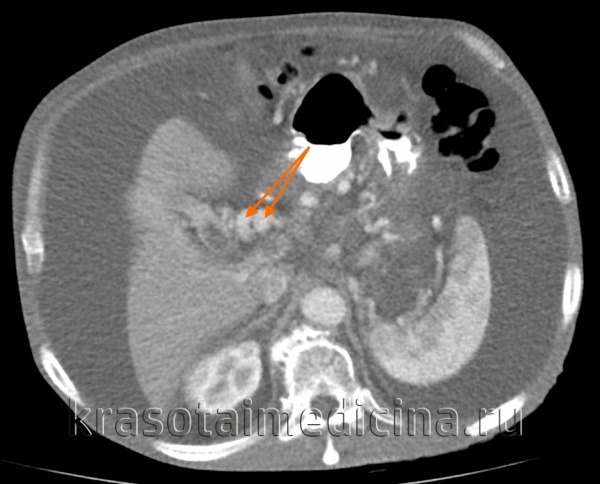

КТ ОБП. Этот же пациент, варикозно расширенные вены как проявление синдрома портальной гипертензии (коричневая стрелка).